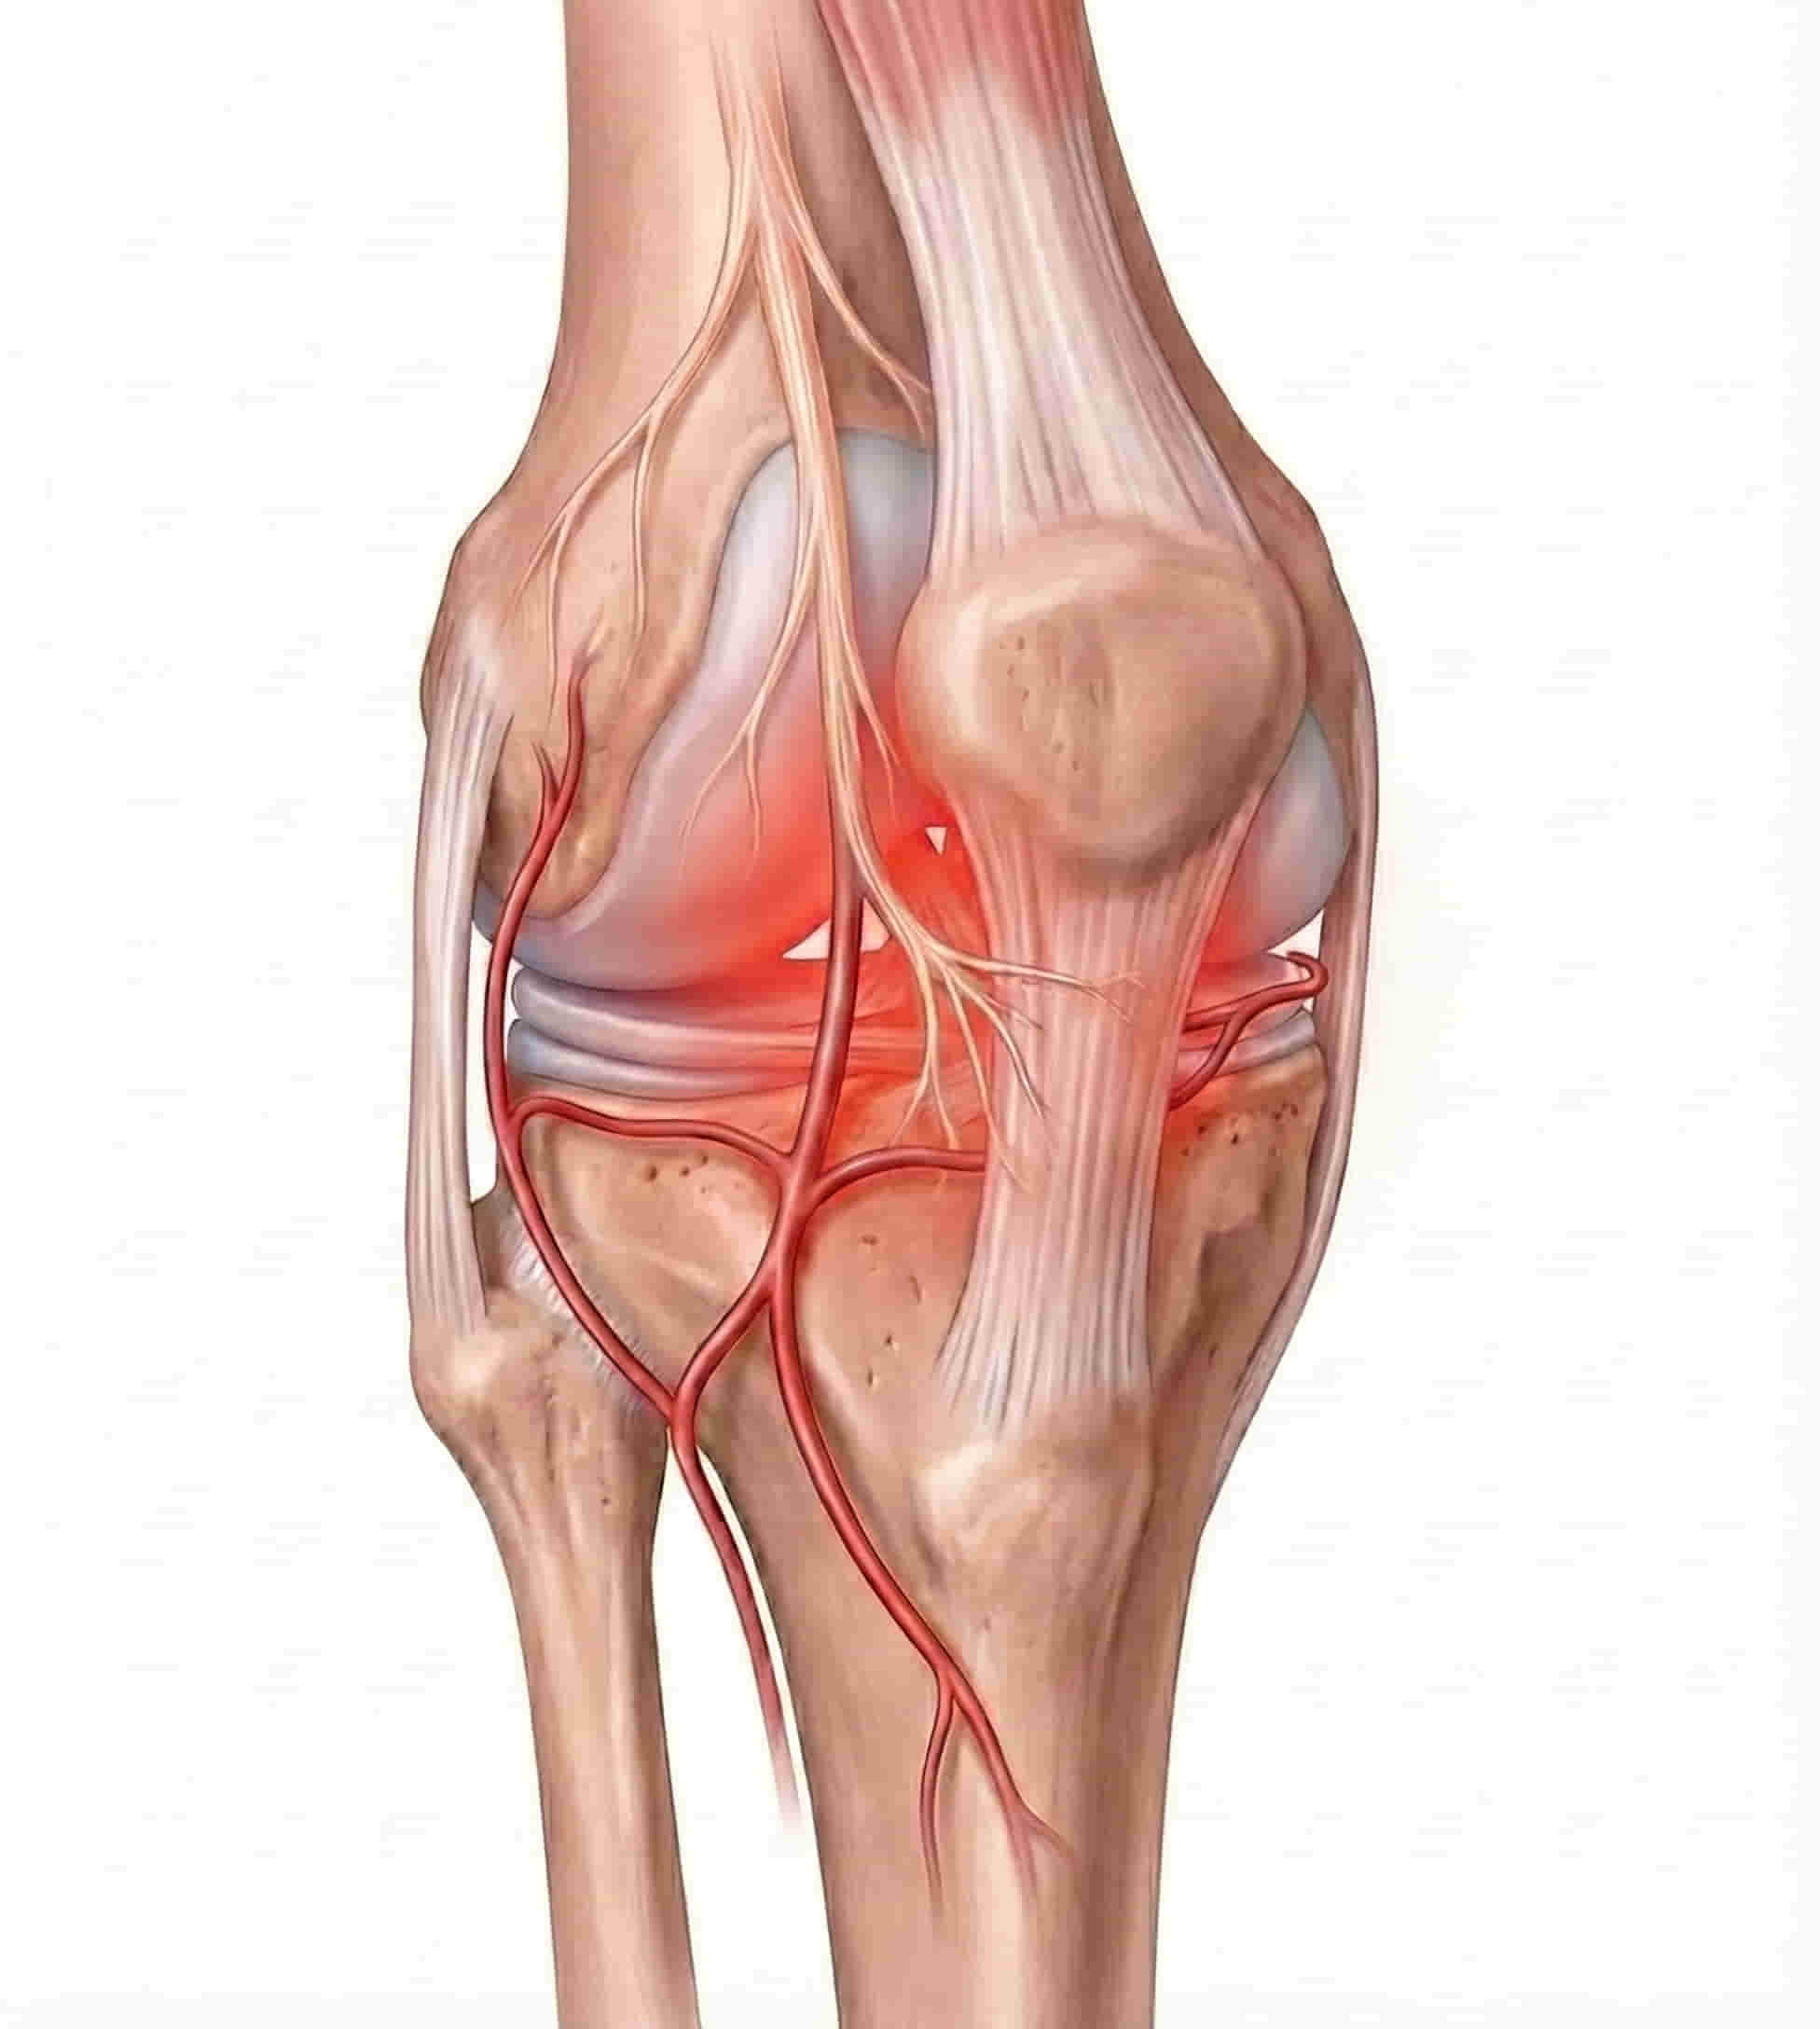

🩺 What Is Genicular Nerve Ablation?

Using thermal energy (Radiofrequency Ablation (RFA) or cold energy (Cryoablation), to “turn off” the specific nerves responsible for transmitting pain signals from the knee joint to the brain. By interrupting these signals, patients can experience long-term pain relief and improved mobility without the need for invasive joint replacement.

🎯 How It Works: Silencing Pain Signals

- Image Guidance: Using real-time X-ray (fluoroscopy), Dr. Ram precisely positions specialized needles near the sensory nerves of the knee.

- Thermal/Cold Ablation: A small amount of radiofrequency/cold energy is passed through the needle, creating a heat/ice lesion on the nerve.

- Signal Interruption: This “stuns” the nerve, preventing it from sending pain messages. The nerve remains intact, but its ability to transmit pain is deactivated.